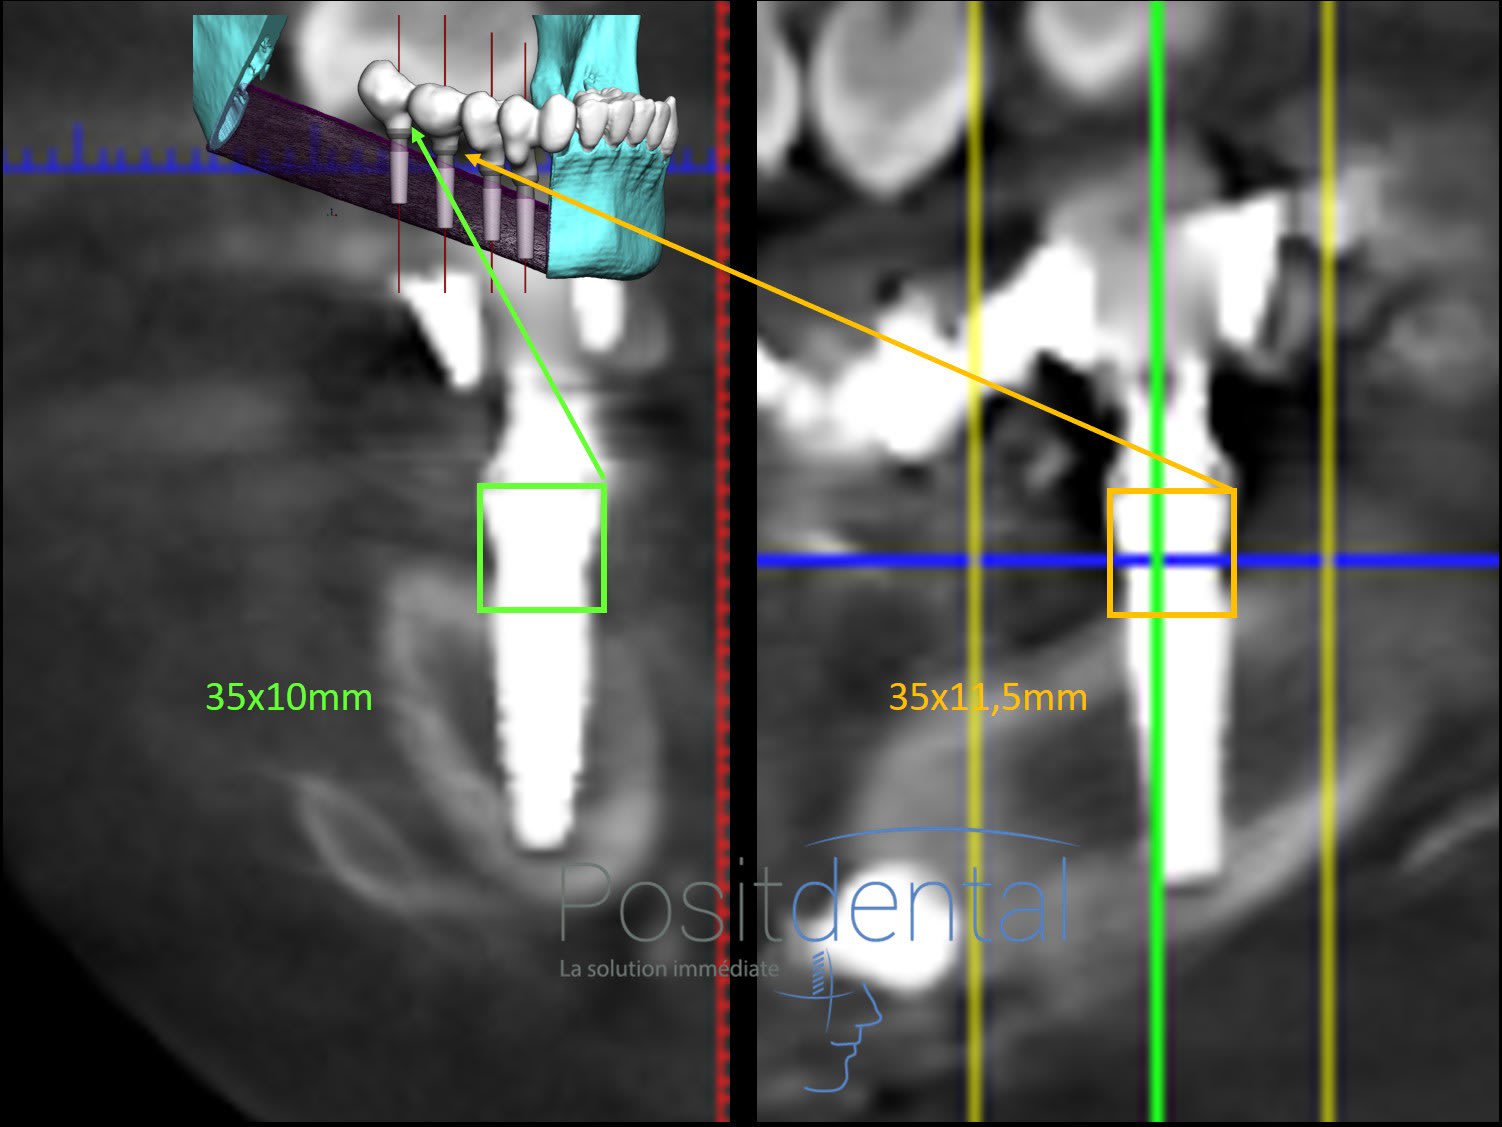

Concernant l'enfouissement, la position, la stabilité des 2 implants postérieur fixés dans la greffe du péroné tout semblait correct lors de la clinique.

La panoramique a permis de vérifier que les piliers MU er provisoires titane sont en place.

La pano semble indiquer pour certain implant un défaut d'enfouissement ou une perforation de la corticale.

L'implant le plus postérieur est un Nobel Active de 10 mm et le suivant 11.5. Tout les MU utilisés sont les + haut de chez Nobel des 4.5. Il me semble que la plate forme du MU fait 4.8 de diamètre. En l'absence de règle pour mesuré les distances il est possible en traçant un carré sur une coupe de scanner d'avoir une idée plus précise que la simple observation.

Etant donné le plan osseux incliné résultant du rapport la position de l'implant et la greffe il a été convenu qu'une partie du col implantaire serait supra osseuse et l'autre infra osseuse. Pour l'ancrage nous avons qu'une corticale fine de moins de 2 mm. Il a été programmé que dans la corticale coté col, les spires s'incèrerons dans la corticale sur le maximum de volume et coté apex sur de 1 mm.

Les coupes scanner confirment que la position des implants distaux correspond à la simulation implantaire assistée par ordinateur.

Sur les coupes tu peux voir que l'enfouissement correspond à la 3D et contrairement à ce qui est dit ils sont en bi corticale

C'est certain qu'en confondant le MU d'une hauteur de 4,5 mm et le col de l'implant tu racontes une énorme ânerie.

Dans le carré vert ou orange c'est le Multi- Unit que tu vois.

Pour ton info, dans ce type de reconstruction implanto-portée sur péroné des MU de 6 à 10 mm seraient adaptés, les 4,5 sont les plus haut disponibles chez Nobel Biocare.

Les donnés des éléments sur l'image où tu as fait les tracés

longueur de l'implant 10 mm c'est un 35 10 Nobel Active

Multi Unit hauteur hauteur 4,5 mm

Ce qui me manque est le diamètre di MU mais si c'est 4,8 mm ton tracé est faux

Merci pour cette belle modélisation Olieve

voici ce que j'obtiens en appliquant un carré avec une hauteur égale à la largeur du MU

Tu en penses quoi par rapport à ton trait rouge sur la coupe scanner?